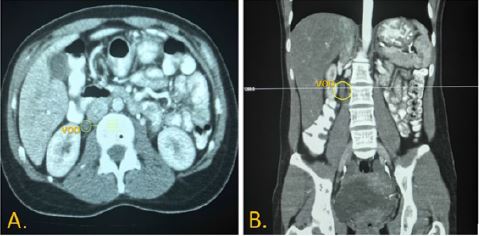

Ante la complejidad sobre la posible etiología del dolor, aunada a los datos que proveyeron la valoración y los exámenes paraclínicos iniciales, a la mujer se le tomó una tomografía abdominal contrastada, que reportó ausencia de opacificación de la vena gonadal derecha, con dilatación de esta ( figura 1), compatible con trombosis de vena gonadal derecha. Dados estos hallazgos imagenológicos, sin antecedentes de eventos trombóticos previos, neoplasia o estado puerperal reciente, contando con el antecedente de aborto espontáneo e historia presumible de autoinmunidad familiar, se sospechó síndrome antifosfolipídico primario.